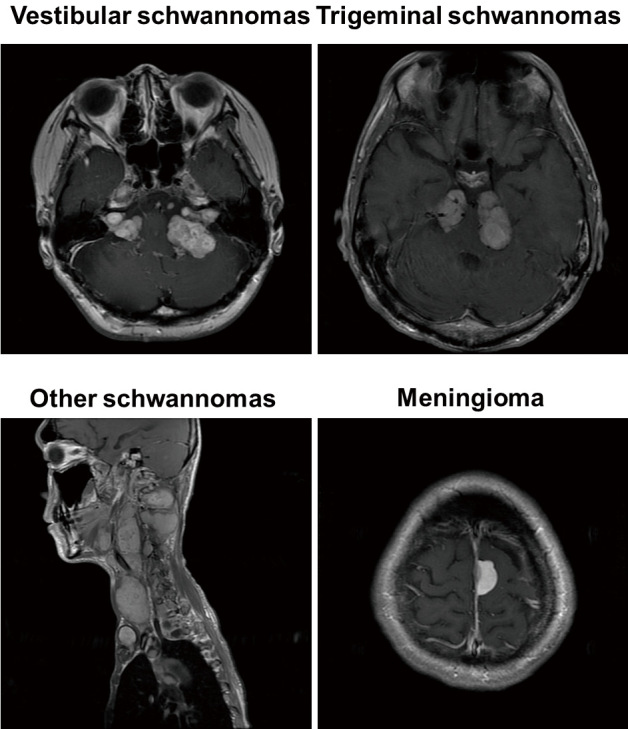

NF2-related schwannomatosis (NF2; previously termed neurofibromatosis type 2) is a tumor-prone disorder characterized by development of multiple schwannomas and meningiomas. The diagnostic criteria of NF2 have been regularly revised. Clinical criteria for NF2 were first formulated at the National Institutes of Health Consensus Conference in 1987 and revised in 1990. Revised criteria were also proposed by the Manchester group in 1992 and by the National Neurofibromatosis Foundation (NNFF) in 1997. The 2011 Baser criteria improved the sensitivity of diagnostic criteria, particularly for patients without bilateral vestibular schwannomas. Revisions to the Manchester criteria were published in 2019, with replacement of "glioma" by "ependymoma," removal of "neurofibroma," addition of an age limit of 70 years for development of vestibular schwannomas, and introduction of molecular criteria, which led to the most widely used criteria. In 2022, the criteria were reviewed and updated by the international committee of NF experts. In addition to changes in diagnostic criteria, the committee recommended the use of "schwannomatosis" as an umbrella term for conditions that predispose to schwannomas. Each type of schwannomatosis was classified by the gene containing the disease-causing pathogenic variant. Molecular data from NF2 patients led to further clarification of the diagnostic criteria for NF2 mosaic phenotypes. Given all these changes, the diagnostic criteria of NF2 may be confusing. Herein, to help healthcare professionals who diagnose NF2 conditions in the clinical setting, we review the historical development of diagnostic criteria.